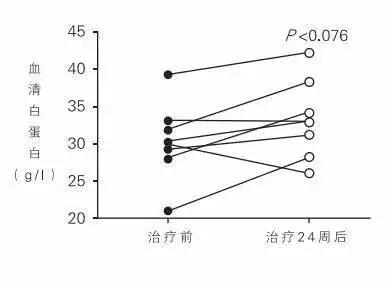

通过干细胞对肝病患者的治疗效果到底如何呢?看看下面这24周临床研究前后对比你就知道了。

恢复肝功能指标

研究显示:干细胞治疗24周可显著升高患者的血清蛋白水平。